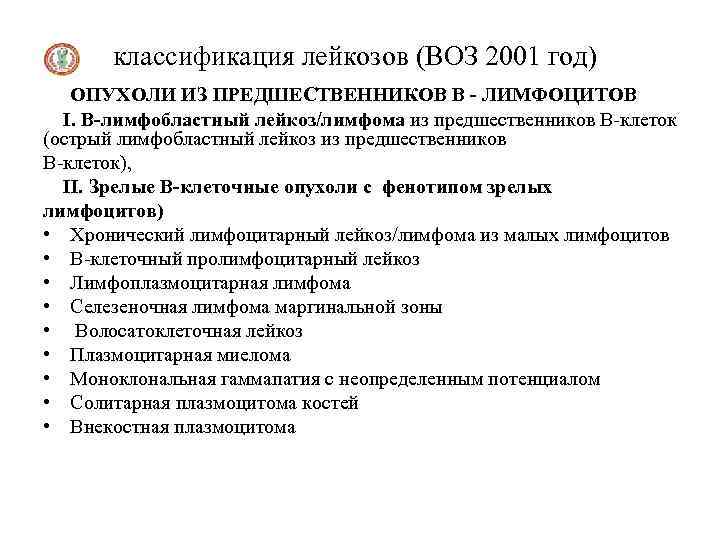

классификация лейкозов (ВОЗ 2001 год) ОПУХОЛИ ИЗ ПРЕДШЕСТВЕННИКОВ В - ЛИМФОЦИТОВ I. В-лимфобластный лейкоз/лимфома из предшественников В-клеток (острый лимфобластный лейкоз из предшественников В-клеток), II. Зрелые В-клеточные опухоли с фенотипом зрелых лимфоцитов) • Хронический лимфоцитарный лейкоз/лимфома из малых лимфоцитов • В-клеточный пролимфоцитарный лейкоз • Лимфоплазмоцитарная лимфома • Селезеночная лимфома маргинальной зоны • Волосатоклеточная лейкоз • Плазмоцитарная миелома • Моноклональная гаммапатия с неопределенным потенциалом • Солитарная плазмоцитома костей • Внекостная плазмоцитома